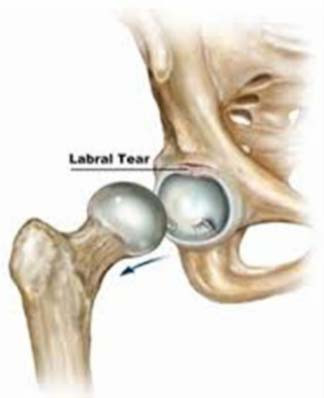

Hip Arthroscopy Rehabilitation

Rehabilitation after hip arthroscopy is essential. It can take a number of months to achieve the desired outcome andwithout input from your physio good results willbe harder to achieve.

Here you will find a comprehensive guide to use with their instruction to achieve good outcomes.

Download Protocol Document